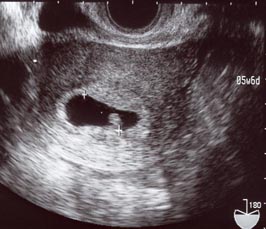

5W6d

2006/06/18 (Sun) - 妊娠初期(~15w)

この前(6/9)に行ったときに貰ったエコー写真は

4週1日って書いてあったけど

6/16に貰ったエコー写真には5週6日と書いてある…。

なんだかなぁ…どっかで時空のねじれが…(嘘)。

それもこれも私のガタガタな基礎体温表がいけないのですよ…。

(しかも、まともに測り始めて1週期目だったからますますわからん)

これが6/16のエコー写真。

この黒い楕円の中の白い豆みたいなのが赤ちゃん。

「こっこちゃん」と呼んでおります。